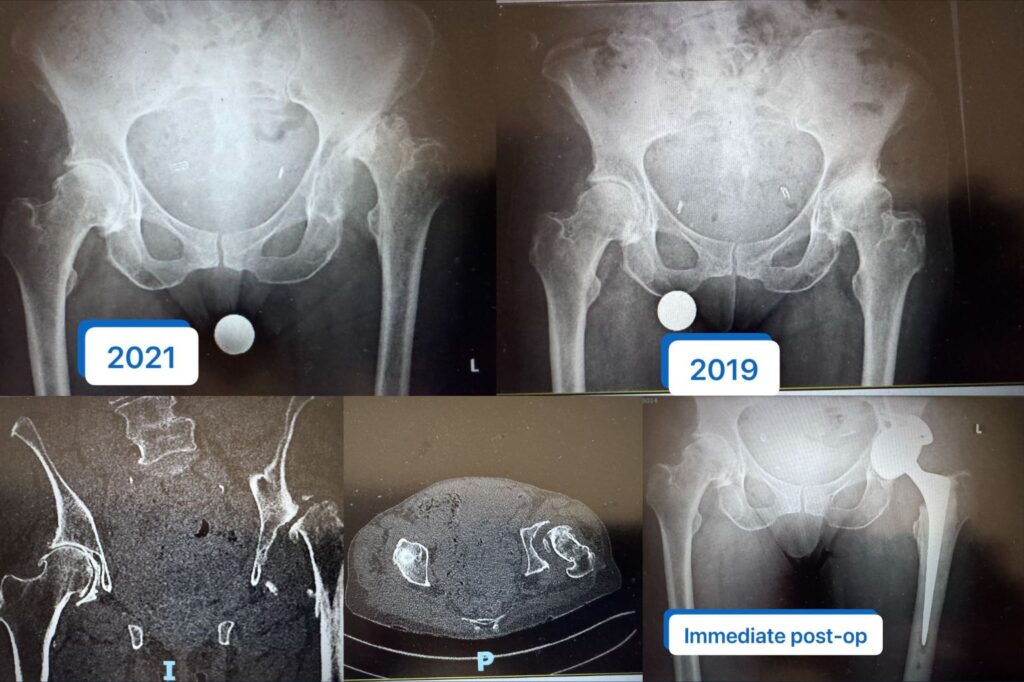

Routine Hip Replacement Turning Complex | Acetabular Reconstruction Case

An 82-year-old patient planned for routine hip replacement developed rapid femoral head collapse and acetabular bone loss, requiring complex acetabular reconstruction. A real-world hip surgery…